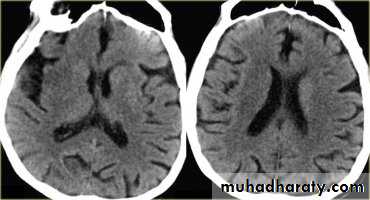

ACUTE INFARCTION

* wedge shape hypo density area.* Shifting of the midline & frontal horn

Chronic infarction

Hypo density area(pore encephalic cyst)Dilated ventricle